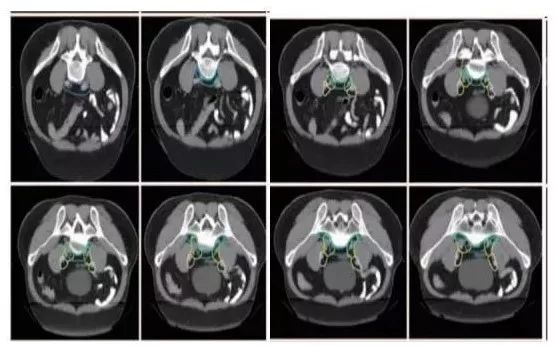

a. 骶前区:骶骨前方区域,包括腹部骶前区⁃PS S (青色) 和盆腔骶前区⁃PS (淡蓝色)(2B 级证据);

b. 直肠系膜区:由全部直肠系膜区以及直肠系膜筋膜组成⁃M(深绿) ;

c. 髂内淋巴引流区⁃LLN P (黄色);

d. 闭孔淋巴引流区⁃LLN A (紫色);

e. 髂外淋巴引流区⁃EI (灰白色);

f. 腹股沟淋巴引流区⁃IN (黄褐色);

g. 坐骨直肠窝⁃IRF (天蓝色);

h. 肛门括约肌复合体⁃SC (桔色)

(b⁃h:1 级证据)。

高危淋巴结引流区及高危复发区边界定义及图谱(CT层厚0.5cm,俯卧位)

勾画图谱